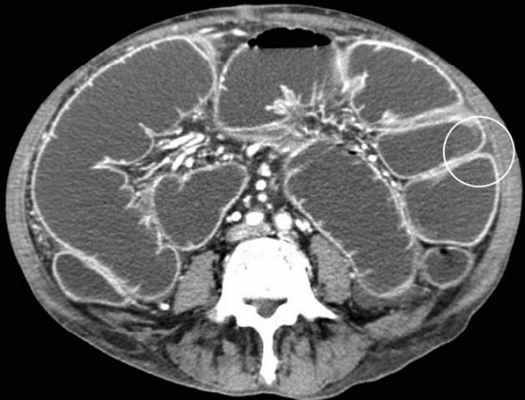

Декомпенсированная форма

Определяются все признаки, описанные при простой форме, дополнительно появляются патологические изменения в брюшной полости:

-расширенные петли тонкой кишки проксимальнее транзиторной зоны (зоны обструкции);

-спавшиеся петли кишечника дистальнее уровня обструкции;

-нормальные не утолщённые стенки кишечника с гомогенным одинаковым контрастным усилением;

-свободная жидкость между расширенными петлями кишечника, зачастую в виде пикантной детали женского туалета-трусиков танга, поэтому в многих источниках описывается как признак "танга" (tanga sign);

-свободная жидкость в брыжеечных карманах;

-свободная жидкость в брюшной полости.

Примеры скопления жидкости между петлями кишечника (танга) и в карманах брыжейки при декомпенсированной форме.